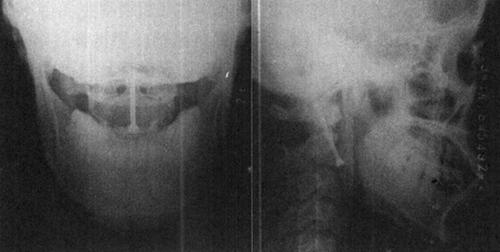

图13-16 单枚螺钉固定齿状突骨折术后X光片

图13-17 两枚螺钉固定齿状突骨折